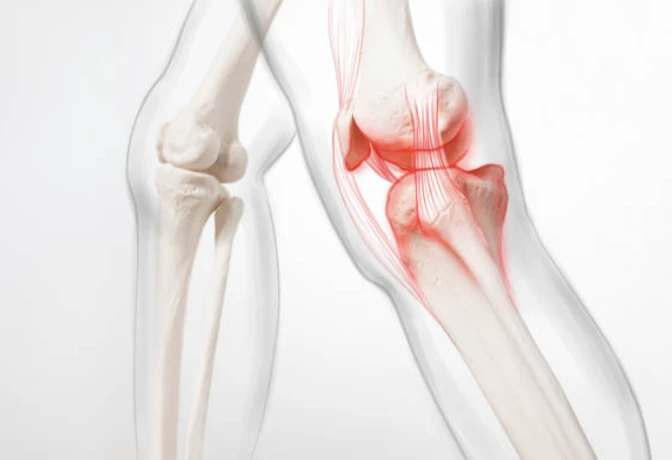

무릎의 구조

무릎이 어떤 부분으로 구성되어있는지 간략하게 살펴보겠습니다. 무릎은 들어 올리기, 무릎 꿇기 등의 일상적인 활동과 걷기 및 달리기, 에어로빅과 같은 고강도 활동으로 인해 많은 스트레스를 받는 취약한 관절입니다. 무릎 통증 원인은 이유가 다양할 수 있습니다.

❏ 무릎의 구성

- 경골 : 정강이 뼈로 하퇴골 안쪽의 크고 단단한 뼈입니다.

- 대퇴골 : 인체에서 가장 길고 단단한 벼로 신장 전체의 4분에 1을 차지합니다.

- 슬개골 : 무릎 관절을 이루고 있는 종지 모양의 오목한 뼈

각 뼈의 끝은 충격을 흡수하기 위해 연골층이 덮여있습니다. 기본적으로 무릎은 근육과 인대 그리고 힘줄에 의해 결합된 2개의 다리뼈입니다.

무릎에는 다리를 곧게 펴는 대퇴사두근(허벅지 앞쪽에 위치)과 다리를 구부리는 햄스트링 근육(허벅지 뒤쪽에 위치)을 포함하고 있습니다.

힘줄은 근육과 뼈를 연결하는 질긴 조직입니다. 인대는 뼈와 뼈를 연결하는 조직의 탄성 밴드와 같은 역할을 합니다. 무릎의 일부 인대는 관절의 안정성과 보호를 제공하지만, 다른 인대는 정강이 뼈의 앞뒤 움직임을 제한합니다.